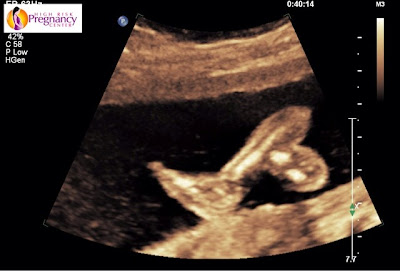

22 Week update!

We had a doctor appointment this week and my OB gave me a few options to consider. Well, actually she gave me two options. I can choose to schedule a repeat c-section at 39 weeks or, if I want to attempt a VBAC (vaginal birth after cesarian) then I can do that but they will not allow me to go past my due date. If I choose to pursue a VBAC, then my c-section would be schedule for my due date (40 weeks) and if I go into labor on my own before then, great. I have until 28 weeks to decide and schedule but I can change my mind later.

I really want to have a VBAC. My c-section recovery was miserable, more painful than I could have expected and I really resented the fact that over 24 hours of labor resulted in a c-section. The plan is to schedule a c-section for 40 weeks and pray I go into labor on my own before then. They will not induce me. I am also being realistic though and know that we will be closely monitored at the High Risk Pregnancy Center for fluid issues and another 9+ pound baby. If we are on track for a similar experience, then I can change my mind and say let's just do this at 39 weeks. So far, things are pretty similar up to this point.

How far along? 22 weeks

Gender: Boy!